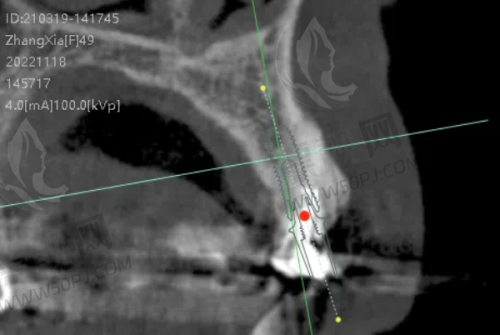

?种植牙:国内外有名品牌全覆盖,医生种植经验多,缺牙烦恼解决快准稳。